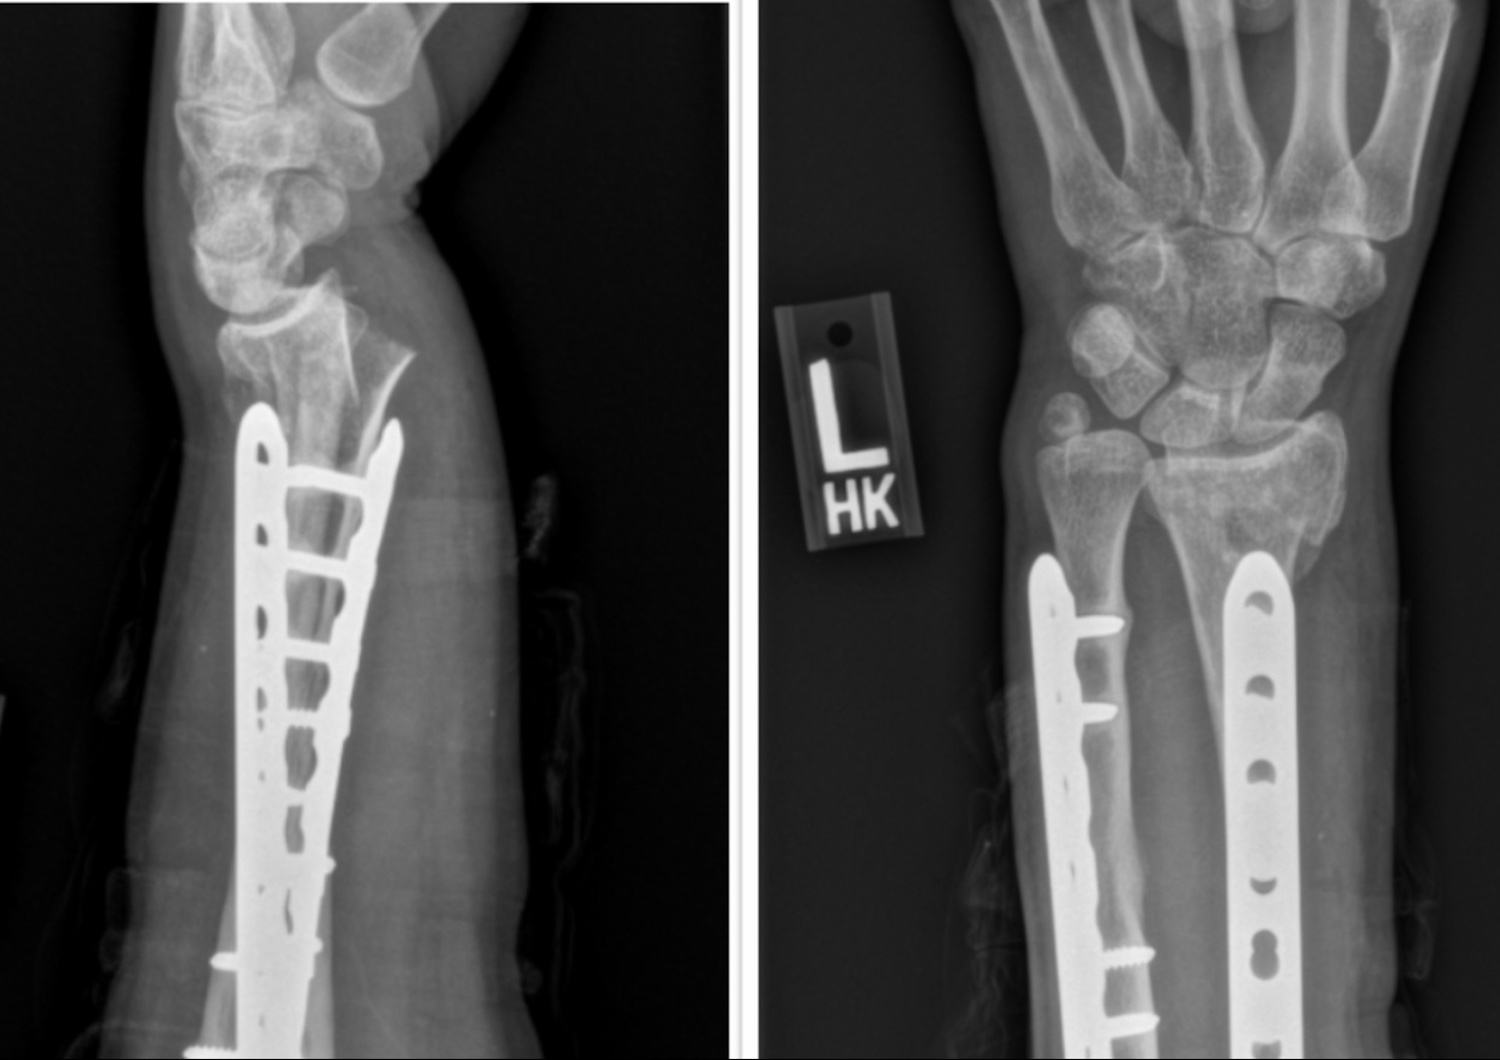

Over a decade ago (16 years to be exact) I broke my left forearm for the first time while snowboarding when I got off balance in the air while sessioning park jumps on a slushy spring day. I instinctively stuck my left arm out straight as the ground quickly approached and when all my body weight, along with the momentum of falling from at least 10 feet up, got directed through my left arm both the radius and ulna (the two long bones in the forearm) were no match and each fractured completely near the middle of the bone. The decision to do surgery was made quickly at the hospital since it would be quite challenging to set (or reduce) both bones to regain proper alignment. A long plate was used to align each bone in a surgery called an open reduction internal fixation (ORIF) and within a few months, I was back to normal use of my left arm and thinking about how lucky I was to have gotten off so easily.

Four years later, as I was slowly improving at mountain biking, I crashed and fractured this same arm again but this time it was much worse. The ulna (the bone on the pinky side of the hand) had a compound fracture, meaning that the bone had come through the skin. The radius (the bone on the thumb side) had also fractured near the end of the plate and this injury ended up requiring two separate surgeries over the next four days that were spent in the hospital in order to remove the previous plates and then put two new plates in to regain proper alignment in both bones. The recovery from these surgeries was much longer than after the first injury four years earlier but still I eventually returned to mountain biking by the next summer. That injury was over nine years ago but the memory of it is still very sharp in my mind, so when I fell off that skinny on the north shore a few weeks ago and stuck my left arm out to break my fall I immediately assumed that I had once again fractured both bones and would surely need surgery. I also quickly came to the conclusion that I would have to find someone to take my spot on a ski trip planned for the end of February but that hopefully, I would be back to biking by at least April although I couldn’t be sure about this. Add to that the new experience of what I can only conclude was my ulnar nerve being compressed (my pinky and fourth finger started feeling like they were on fire and eventually became all I could focus on at the hospital until after the fracture was reduced) hopefully it’s now easier to understand my incredible gratitude that the orthopedic surgeon at the hospital was able to reduce my fracture so well that I won’t end up needing surgery for this one.

Pre and post reduction of the recent distal radius fracture with plates from the previous arm fracture. Photo credit: St. Joseph Hospital and Polyclinic Orthopedics